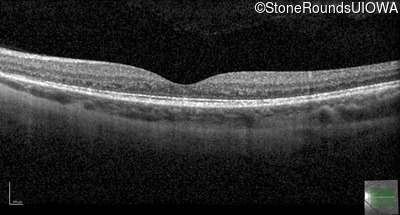

Optical Coherence Tomography - Right - 20/50 +2

Exemplar / OCT Stack

OCT Stack